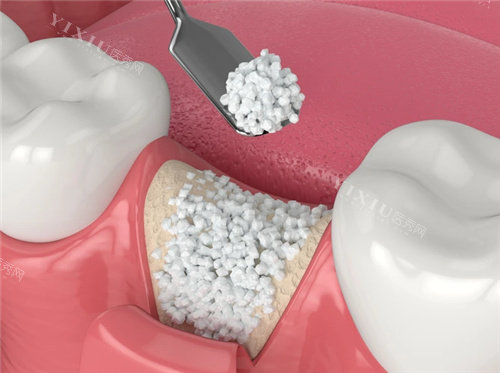

骨增量手术风险高:植骨手术需额外植入人工骨粉,术后感染率增加20%,且需等待6个月骨愈合期;

2. 骨整合效率

SLA表面处理:通过大颗粒喷砂+酸蚀技术,将种植体表面粗糙度提升至Ra2.5μm,骨结合速度较传统种植体提升40%;

平台转移设计:基台直径比种植体小0.5mm,引导骨组织向种植体颈部生长,减少边缘骨吸收。